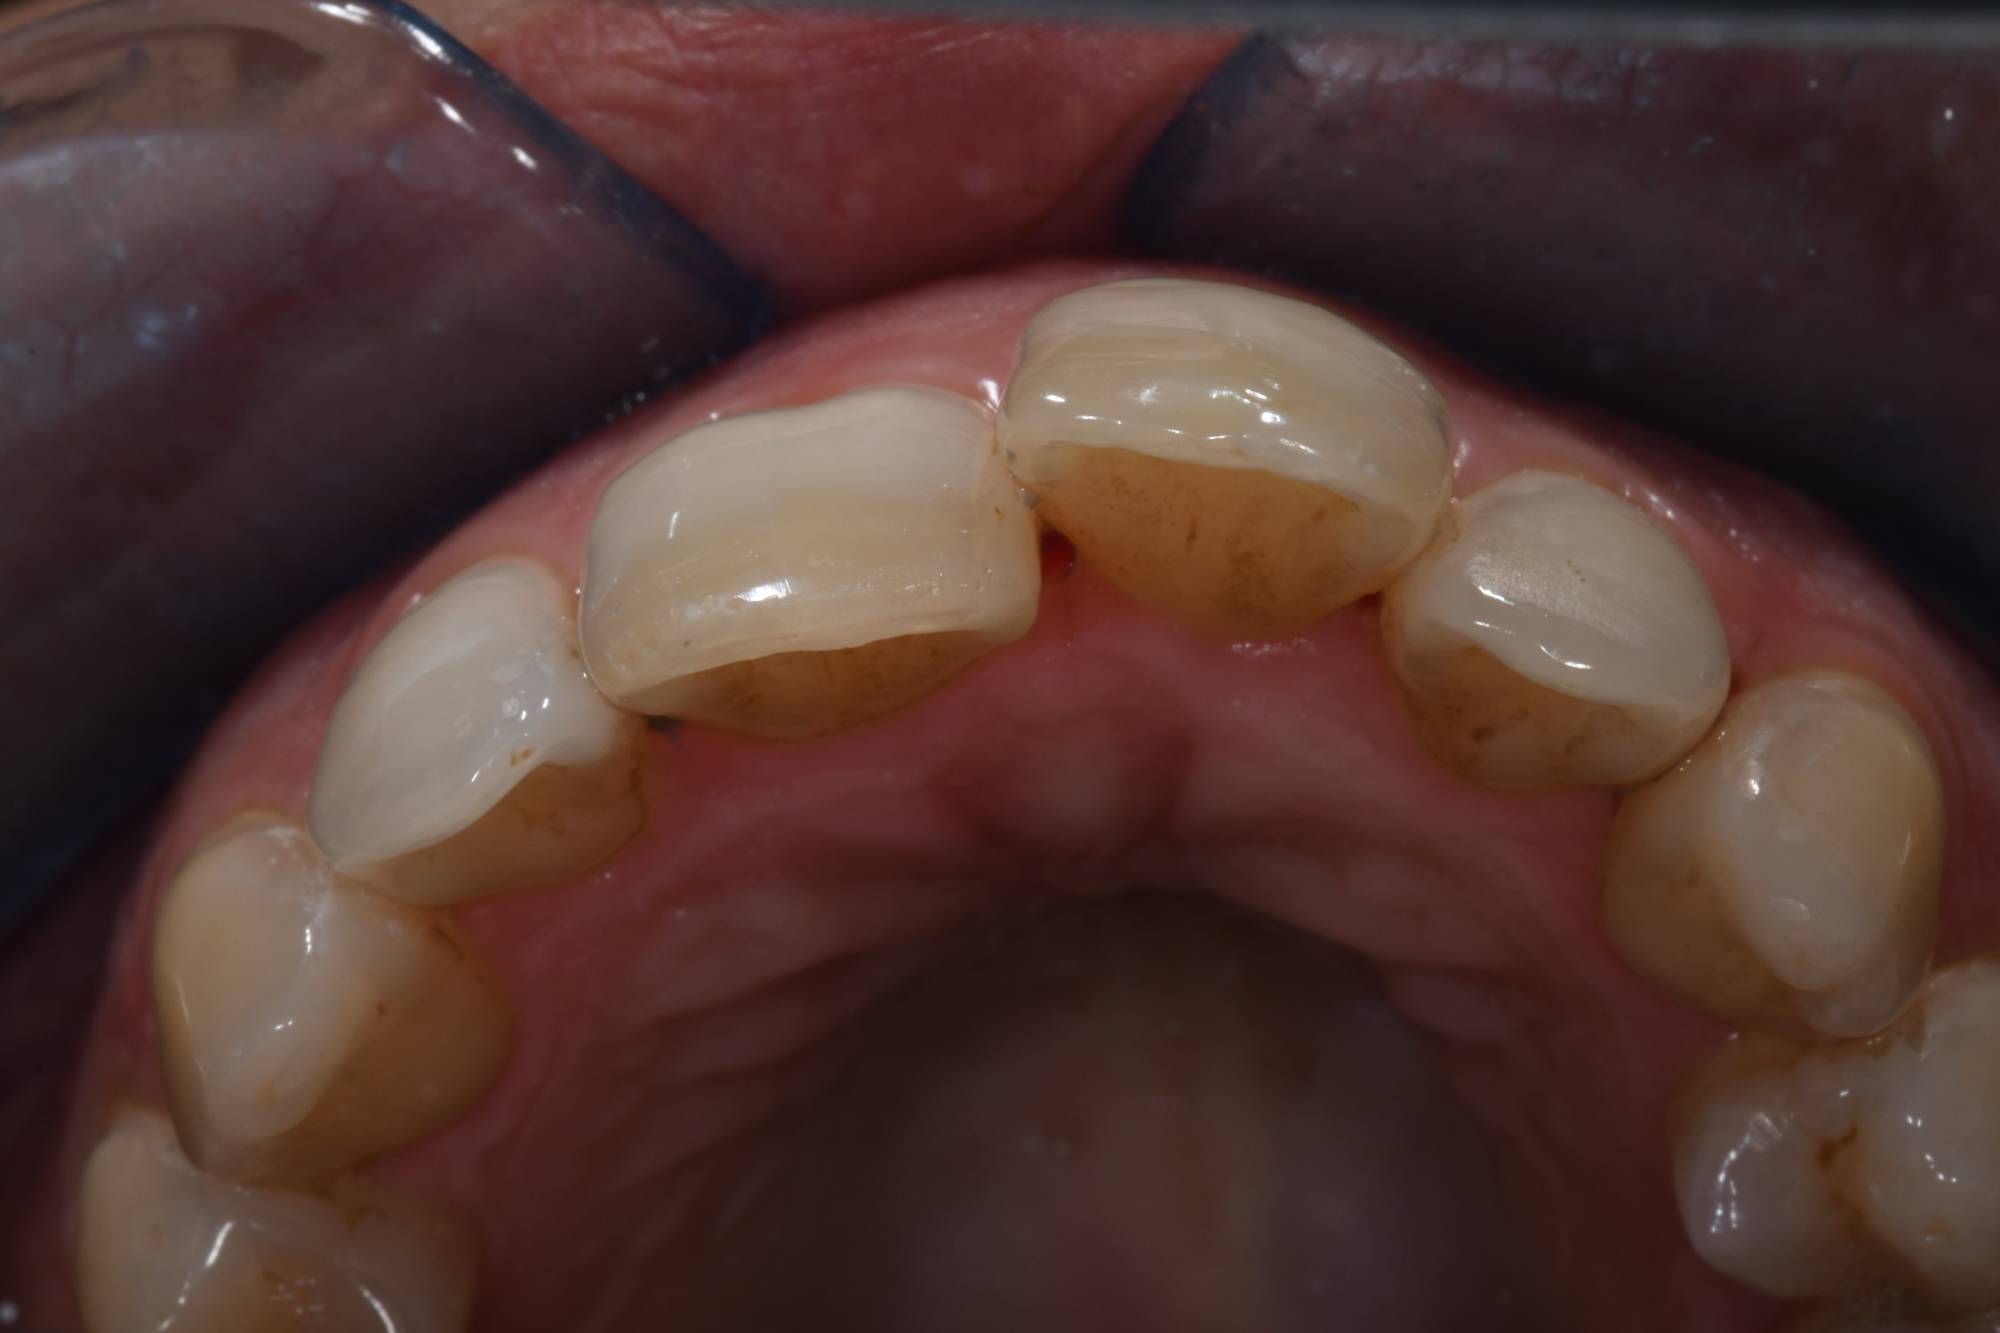

La buona notizia è che puoi tornare a sorridere con gli allineatori trasparenti! Guarda le foto qui sotto: la signora aveva un incisivo che sporgeva talmente tanto che non poteva chiudere le labbra e si vergognava di sorridere. Viveva quel dente in fuori come una deformità, ma non voleva mettere l’apparecchio tradizionale, si riteneva troppo “vecchia”.

Fortunatamente esiste questa nuova tecnologia che le ha permesso di allineare i suoi incisivi, come vedi nella seconda foto, senza apparecchio fisso e in tempi rapidi.